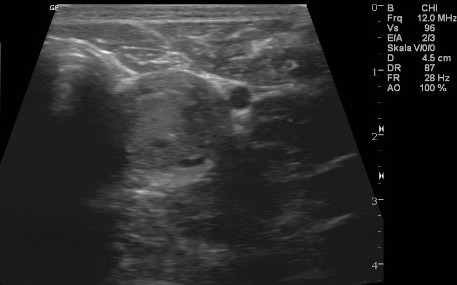

Niere und Harnableitendes System

Akute- und chronische Erkrankungen der Blase- und der Niere werden nicht selten unterschätzt. Einen Funktionsverlust der Nieren kann man im Akutfall nur mit sofortiger intensiver Therapie beheben und den chronischen Funktionsverlust nur Aufhalten jedoch selten noch ausheilen. Harnstoff und Kreatinin sind Funktionsparameter der Niere die erst verändert sind, wenn 80% des Nierengewebes bereits funktionslos geworden sind. Frühere Marker sind der SDMA-Marker und die UPC.

![]() |